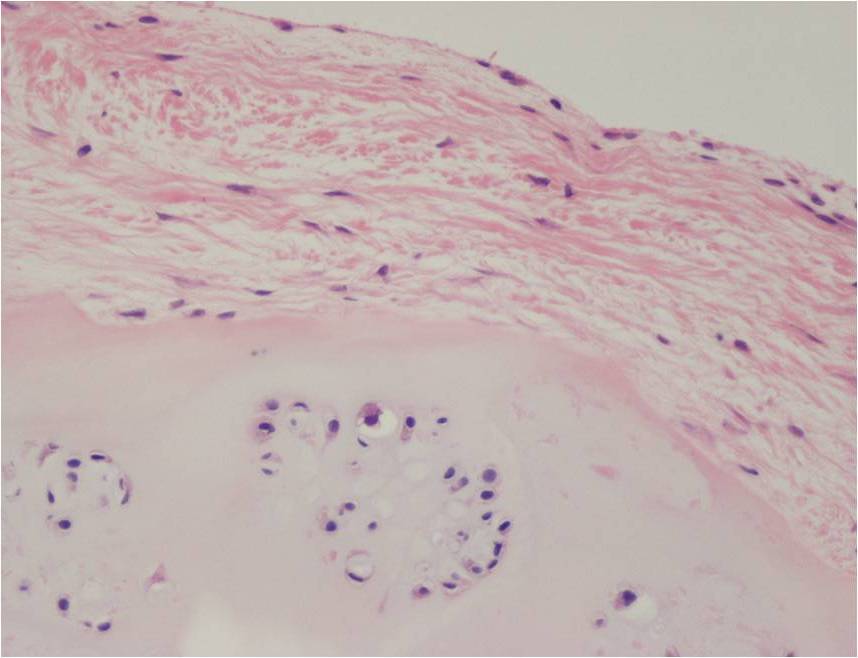

Synovial chondromatosis is an uncommon, benign, process that occurs in large joints, such as the knee (50%), hip, elbow, or shoulder. This process mainly affects synovium and hence most commonly arises from joints and tendons which are lined by synovium. Synovial Chondromatosis may also affect bursae and extend into surrounding soft tissues. This condition is seen in patients between 20 and 50 years of age and most commonly in men (male-female ratio of 2-4/1). The patient usually complains of pain, stiffness, crepitance, swelling, and joint locking. The knee is the most common site to be affected. Symptoms are long-standing and progressive. The plain x-ray may be normal (5 to 33%) or there may be small flecks of calcification (Fig. 1 & 2). On MRI the nodules of cartilage are easily seen. MR imaging may also show synovial thickening, joint erosions and intraarticular calcifications. The signal characteristics of these intraarticular bodies depend of their composition. If mineralization is not present the signal intensity follows the cartilage signal with intermediate signal on T1 images and high signal on T2 weighted MR images. Uniformly calcified bodies follows bone density on all sequences with bone marrow signal centrally and low signal peripherally (Fig. 3-5). Histologically the cartilage is arranged in nodules, which are quite cellular (Fig. 7-9). Synovial lining is present surrounding the cartilage nodules (Fig. 8). The cartilage nodules are often referred to as loose bodies however they are not really loose and embedded in the synovium lining. This is considered a metaplastic condition as opposed to a true neoplastic condition. Rarely it may turn into a malignancy usually a low grade chondrosarcoma. Malignant change is suggested by deep erosions into adjacent bone.

Fig. 7 – 9. Microscopic Pathology. Low (Fig. 7) and intermediate (Fig. 8 & 9) magnification demonstrates nodules of cartilage with high cellularity. Synovial lining is present surrounding the cartilage nodules.